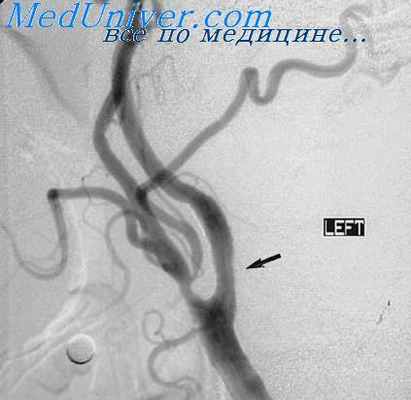

Показанием к каротидной ангиографии является очаг поражения в полушариях (опухоль, абсцесс, киста, внутричерепные гематомы, аневризмы), к вертебральной — подозрение на опухоль, аневризму в задней ямке черепа и бассейне задней мозговой артерии, к тотальной — подозрение на аневризму или опухоль при отсутствии симптомов очагового поражения мозга; к селективной — при необходимости раздельного контрастирования магистральных и более мелких сосудов.

При опухолях мозга могут отмечаться как прямые, так и косвенные симптомы. Так, глиобластомы и менингиомы нередко характеризуются ангиографической картиной сосудистой опухоли. На снимках, особенно в капиллярной фазе, видна сеть новообразованных сосудов. При малососудистых опухолях о наличии объемного процесса можно судить лишь по смещению магистральных сосудов. Для абсцессов мозга характерен бессосудистый участок. При субдуральных гематомах типичен сегментарный бессосудистый участок между костью и мозгом, отжатым кнутри, при этом передняя артерия большого мозга смещена в противоположную сторону, средняя — книзу или кнутри.

Аневризмы контрастируются в виде мешочка округлой или овальной формы, соединенного ножкой (шейкой) с сосудом, из которого они происходят Артерио-венозные мальформации представлены клубком уродливых разветвляющихся сосудов, иногда довольно крупных размеров, с приводящими и отводящими артериальными и венозными сосудами.

Геморрагический инсульт на ангиограммах характеризуется картиной, сходной с кистозной опухолью мозга: смещение магистральных сосудов и бессосудистый участок, соответствующий локализации внутримозговой гематомы. Ишемический инсульт, развивающийся на фоне тромбоза, стеноза или патологической извитости магистральных сосудов шеи, имеет типичную картину, обусловленную вышеназванными сосудистыми изменениями, а также обнаруживается культя, часто конусовидной формы (тромбоз), сужением сосуда концентрически либо эксцентрически за счет атероматозной бляшки на стенке сосуда.